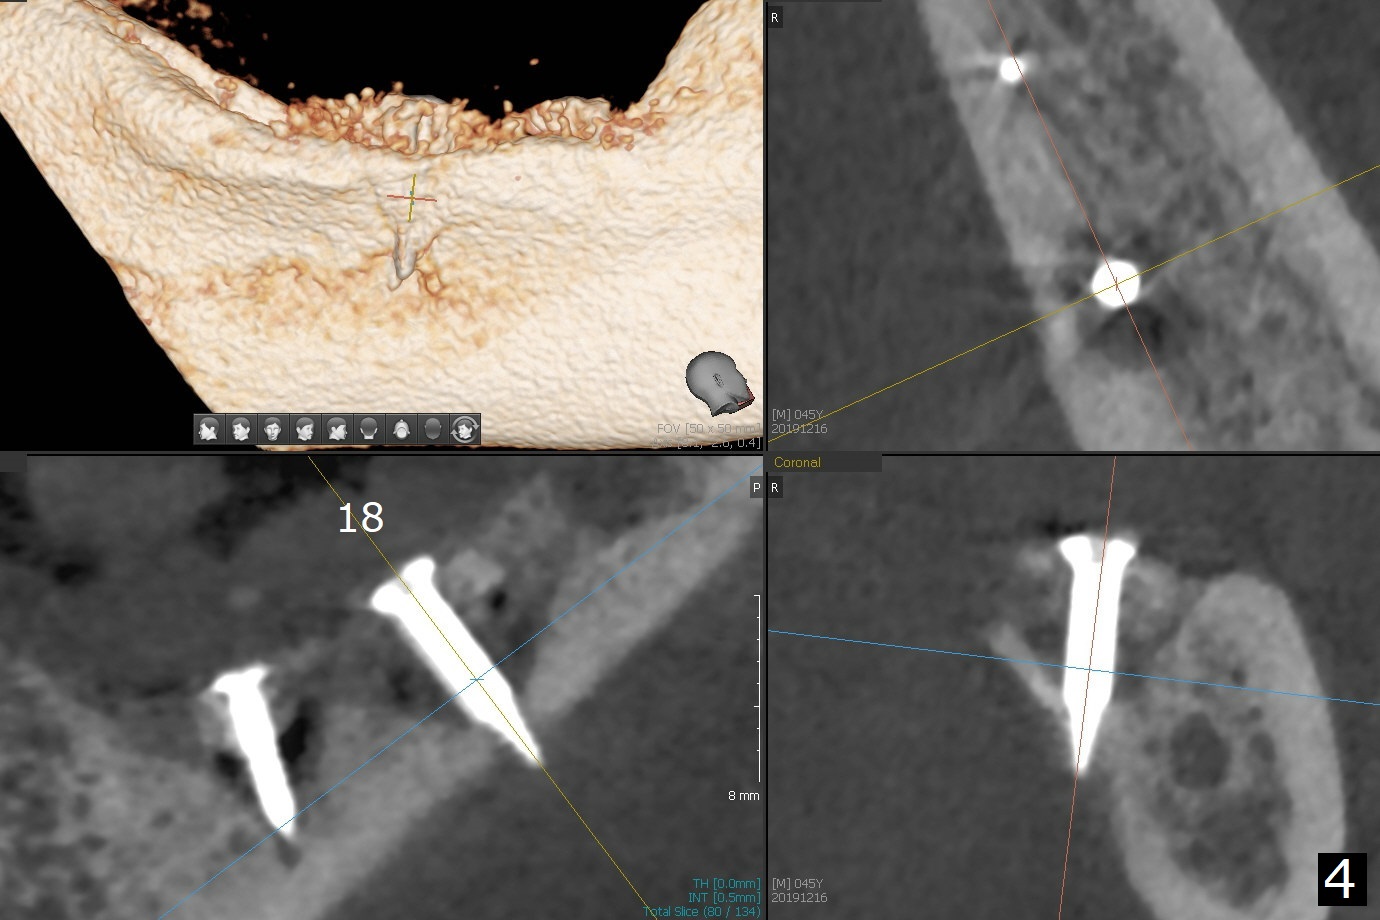

While the implant at #18 is easily removed, the one at #19 is superficial with buccal nonkeratinized gingiva (Fig.1). The latter is removed. Two small pieces of onlay graft is harvested from the left ramus and fixed in the defects with pins (Fig.2), surrounded by allograft with PRF. Since the pin at #18 looks violating the Inferior Alveolar Canal (Fig.2 C), CT is taken. In fact the pin perforates the lingual plate at #18 (Fig.4, as compared to Fig.3 (#19)). It leaves in place. Postop the wound dehisces with loss of allograft and exposure of the screws. The wound heals gradually mesiodistal with exposure of #18 screw 2.5 months postop. Follow up is disrupted by coronavirus pandemic.

It appears that short implants could be placed mesial to the original sites (Fig.5,6), 5x6 and 5x5 mm at #19 and 18, respectively, with guide as lingual as possible. The exposed buccal threads will be covered by 3-D Bond (Fig.9 white line, post decortication (red)), collagen plug and PGA suture. Healing screws are most likely used, although healing abutments should be prepared if they help wound closure.